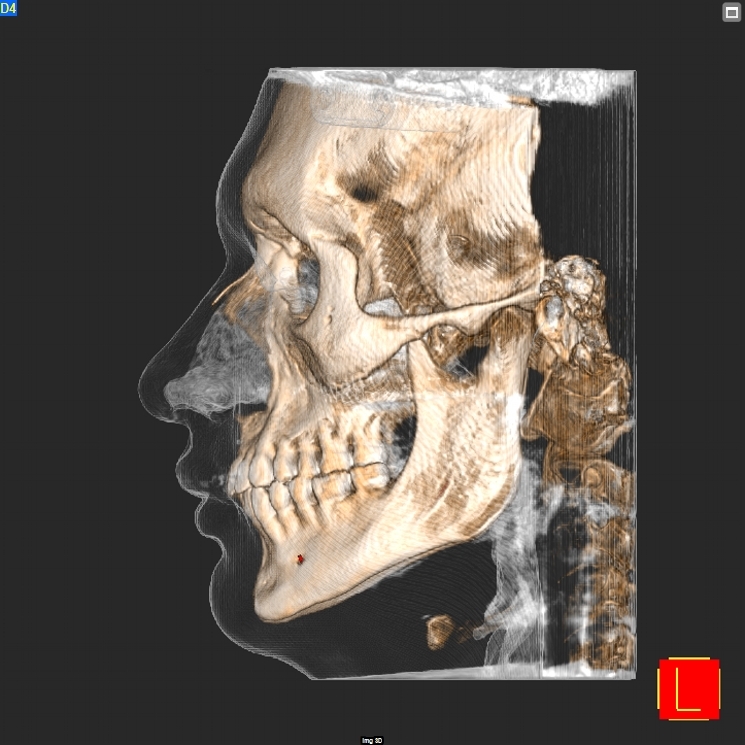

Contamos con estudios avanzados de tomografía dental Cone Beam (CBCT), desde 6x6 hasta 16x18cm.

Imágenes 3D de alta resolución para diagnósticos complejos y planificación de implantes.